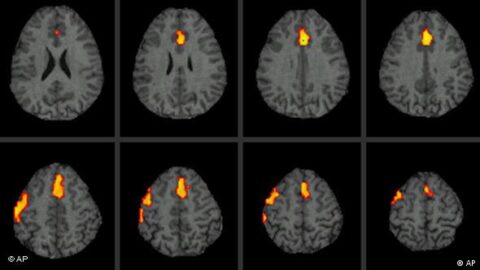

실로시빈은 세로토닌(5-HT) 유사체로서 뇌의 5-HT2A 수용체에 작용한다. 특히 전두엽 피질과 후방대상피질(posterior cingulate cortex), 기본모드네트워크(default mode network, DMN) 등 자아감 형성에 핵심적인 신경망에 영향을 주어, 기존의 사고 패턴을 유연하게 만드는 것으로 알려져 있다. 우울증 환자의 경우 지나치게 경직된 사고 회로와 반복적 부정 사고 루프가 DMN에서 활성화되어 있는데, 실로시빈은 이 네트워크를 일시적으로 해체해 자아 해체 경험을 유도하고 인지적 ‘재설정(reset)’을 유도한다는 이론이 제기되고 있다.